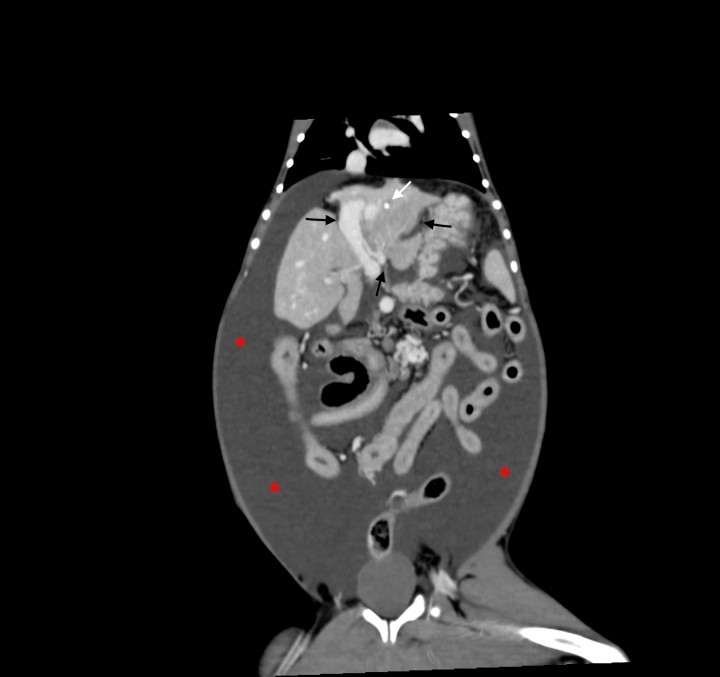

La ecografía abdominal, realizada bajo sedación del paciente y con sonda convexa de 3-9 MHz y lineal de 5-14 MHz (Z.One ultra, ZONARE, Mountain View, CA, EE.UU), evidenció que la vena porta principal a su entrada en el hígado presentaba un flujo unidireccional, pulsátil e invertido (hepatófugo), con velocidad portal de 57 cm/s (Fig. 1), lo que provocaba hipertensión portal y ascitis severa. Además, se observaba una estructura tubular anecoica que comunicaba con la vena porta intrahepática en el lóbulo hepático izquierdo (Fig. 2). Se apreció también una reducción del tamaño del parénquima hepático, de bordes irregulares. Múltiples vasos tortuosos fueron evidenciados caudomedial y lateral al riñón izquierdo (Fig. 3). El páncreas se encontraba aumentado de volumen con parénquima normoecoico y estriado, compatible con una edematización de la glándula (Fig. 4).

<p>Imagen ecográfica en un corte longitudinal de la paciente con Doppler color y pulsado. Se observa un flujo pulsátil e invertido (hepatógufo) de la vena porta principal.</p>

Imagen ecográfica en un corte longitudinal de la paciente con Doppler color y pulsado. Se observa un flujo pulsátil e invertido (hepatógufo) de la vena porta principal.

La TC reveló una microhepatía asimétrica, con los lóbulos hepáticos izquierdos de menor tamaño que los derechos y focos de mineralización distrófica, un gran volumen de efusión abdominal (Fig. 5) y edema de páncreas. El tronco celíaco se encontraba anormalmente dilatado y la aorta abdominal caudal a éste disminuida de tamaño (Fig. 6).

<p>Imagen de tomografía computarizada dorsal tras la administración de contraste intravenoso, ventana de tejido blando. Se observa una microhepatía asimétrica con los lóbulos hepáticos izquierdos de menor tamaño que los derechos (flechas negras) y foco de mineralización distrófica en el parénquima hepático (flecha blanca). Presencia de gran cantidad de líquido libre abdominal (*).</p>

Imagen de tomografía computarizada dorsal tras la administración de contraste intravenoso, ventana de tejido blando. Se observa una microhepatía asimétrica con los lóbulos hepáticos izquierdos de menor tamaño que los derechos (flechas negras) y foco de mineralización distrófica en el parénquima hepático (flecha blanca). Presencia de gran cantidad de líquido libre abdominal (*).